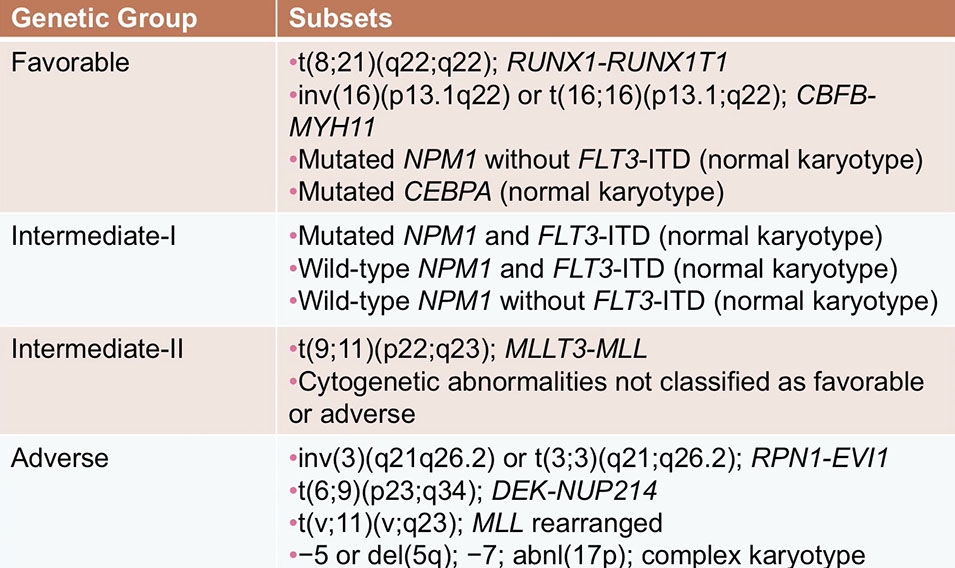

Acute myeloid leukemia (AML) with recurrent genetic abnormalities

- Acute myeloid leukemia with t(8;21)(q22;q22.1); RUNX1-RUNX1T1

- Acute myeloid leukemia with inv(16)(p13.1q22) or t(16;16)(p13.1;q22); CBFB-MYH11

- Acute promyelocytic leukemia (APML) with PML-RARA

- Acute myeloid leukemia with t(9;11)(p21.3;q23.3); KMT2A-MLLT3

- Acute myeloid leukemia with t(6;9)(p23;q34.1); DEK-NUP214

- Acute myeloid leukemia with inv(3)(q21.3q26.2) or t(3;3)(q21.3;q26.2); GATA2, MECOM

- Acute myeloid leukemia (megakaryoblastic) with t(1;22)(p13.3;q13.1); RBM15-MKL1

- Acute myeloid leukemia with BCR-ABL1

Acute myeloid leukemia with gene mutations

- Acute myeloid leukemia with mutated NPM1

- Acute myeloid leukemia with biallelic mutation of CEBPA

- Acute myeloid leukemia with mutated RUNX1

Acute myeloid leukemia with myelodysplasia-related changes

Therapy-related myeloid neoplasms